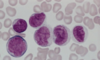

What is this? What can you distinctively see that indicates that?

Acute promyelocytic leukemia, M3

Can clearly see the Auer Rods